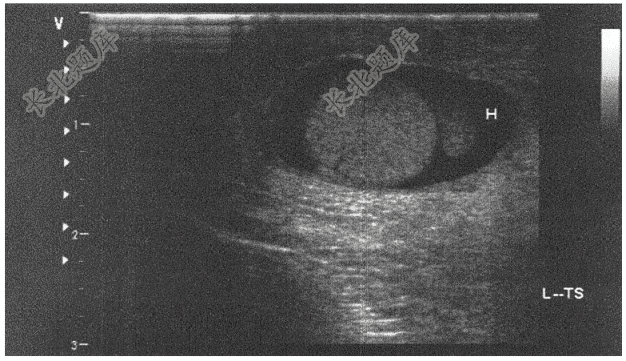

- 单项选择题患者男,35岁。发现阴囊增大半年,无不适感,超声检查如下图,最可能的诊断是( )

E、睾丸鞘膜积液